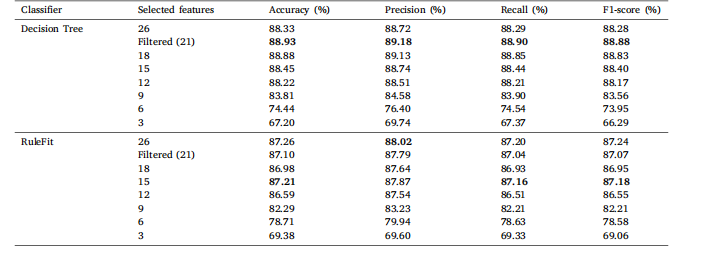

Table 7Classification results of COVID-19 Radiography Database on a comprehensive set of statistical features with varying feature counts for DT andRuleFit

表7 基于不同数量统计特征的COVID-19放射影像数据库分类结果(针对决策树(DT)和RuleFit模型)。